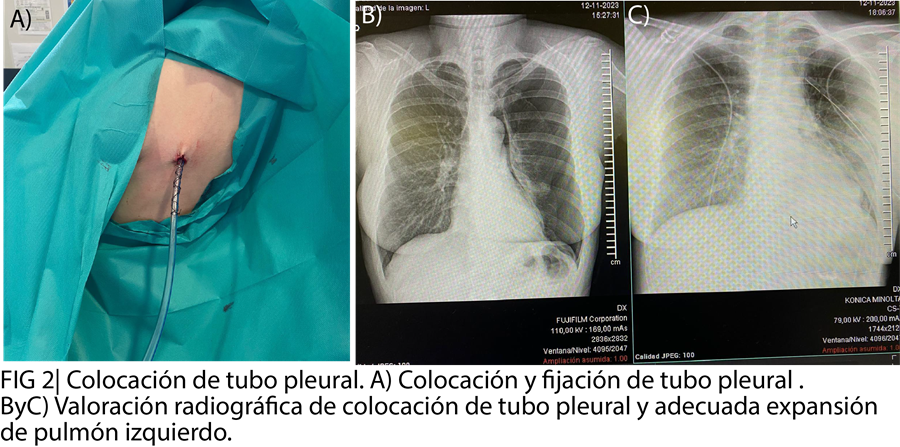

El tratamiento del neumotórax traumático incluyó drenaje torácico guiado por ecografía para reexpandir el pulmón. Se priorizó la analgesia adecuada y la monitorización clínica y radiológica. Plan: seguimiento de la expansión pulmonar y prevención de complicaciones. Ingreso a cargo del servicio de cirugía.

En este caso, la ecografía clínica permitió identificar hallazgos clave: ausencia de deslizamiento pleural, presencia de líneas B, signo de código de barras y ausencia de pulso pulmón. Aunque no se observó el pulso pulmón, que tiene menor sensibilidad, se confirmó el diagnóstico mediante radiografía de tórax, evidenciando fractura costal y neumotórax traumático izquierdo. La colocación de un tubo de tórax ecoasistido permitió la expansión parcial del pulmón y facilitó un manejo seguro, con ingreso hospitalario para seguimiento y monitorización.